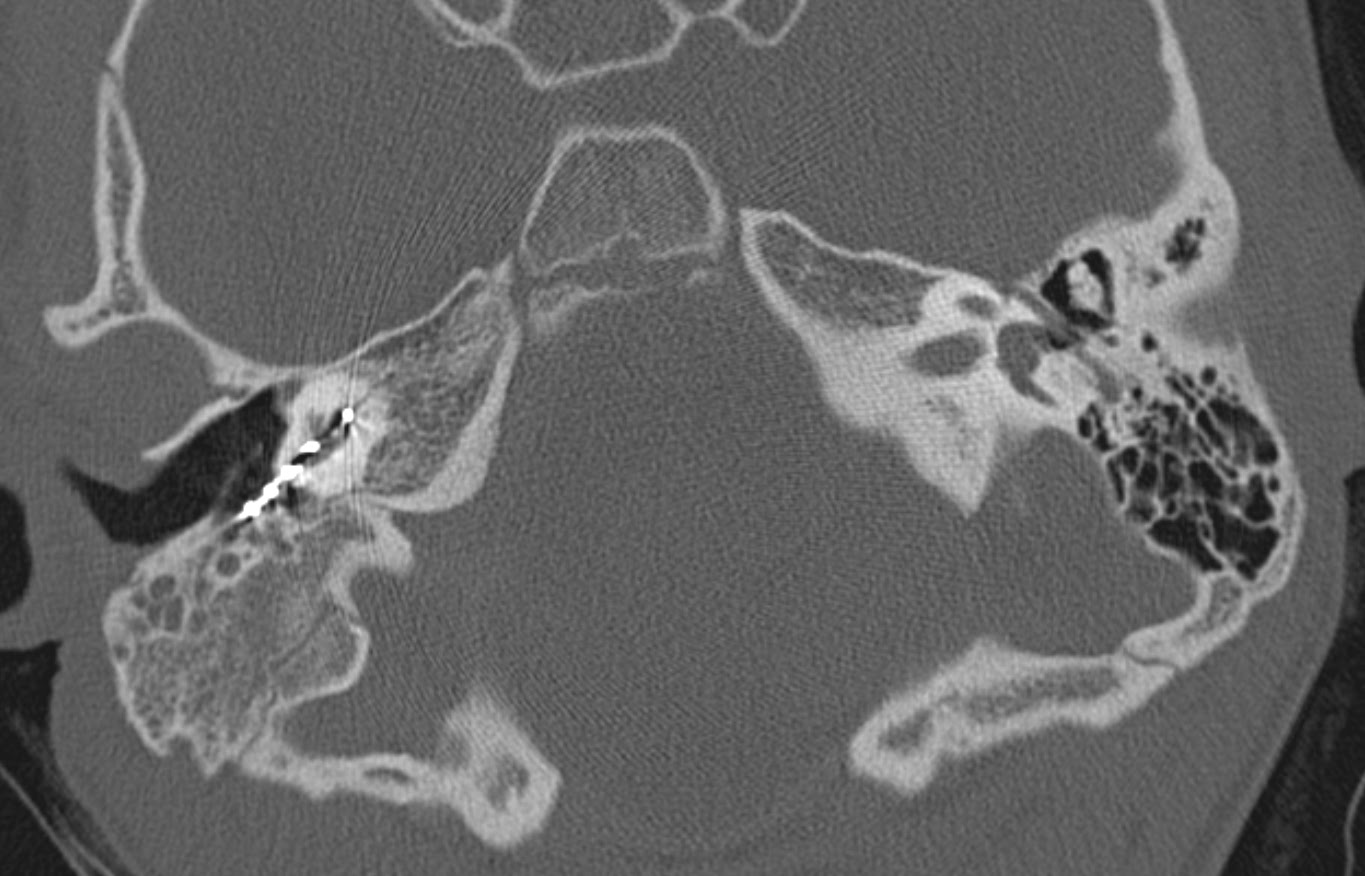

Компьютерная томография височной кости при отосклерозе: диагностика и результаты